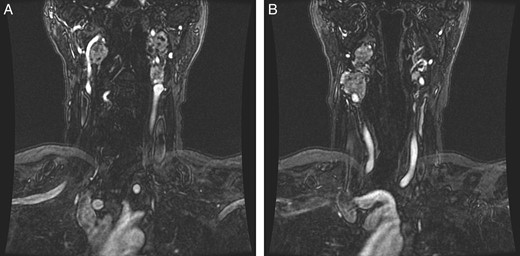

Radiation therapy was selected in the setting of local extension of the tumors and proximity to critical neurovascular structures. The patient underwent stereotactic radiation treatment of 30 Gy over 5 days, with a positive response on imaging (Fig. 2) and a reduced frequency of syncopal events.

(A and B) Magnetic resonance images, coronal planes, highlight three of the four previously noted cervical PGLs decreasing in size, with the right inferior PGL remaining unchanged.